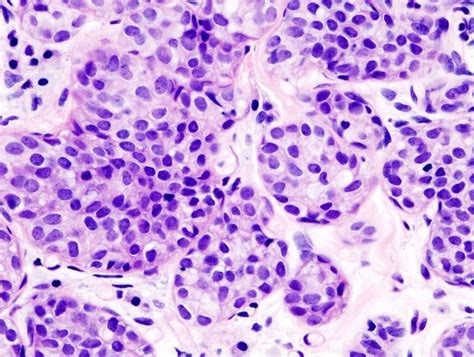

First off, what exactly is invasive breast carcinoma of no special type? Well, in the simplest terms, it’s a type of breast cancer that has spread beyond the milk ducts or lobules into the surrounding breast tissue. The “no special type” part means that the cancer cells don’t have any specific distinguishing features that would classify them into another subtype, like lobular, tubular, or mucinous carcinoma. It’s essentially the most common form of invasive breast cancer, accounting for a significant chunk of all cases. When pathologists examine the tissue under a microscope, they don’t see any unique patterns or characteristics that would lead them to classify it differently. This lack of specific features doesn’t make it any less serious, but it does mean that treatment approaches are generally based on the stage and grade of the cancer, as well as hormone receptor status and HER2 status. The importance of accurate classification cannot be overstated, as it directly impacts patient care and prognosis. Diagnostic procedures such as mammograms, ultrasounds, and biopsies play a crucial role in identifying and characterizing these tumors. Further molecular testing often helps refine treatment strategies, ensuring that each patient receives the most effective and personalized care possible. Understanding the nuances of this diagnosis is key for both healthcare professionals and patients alike.